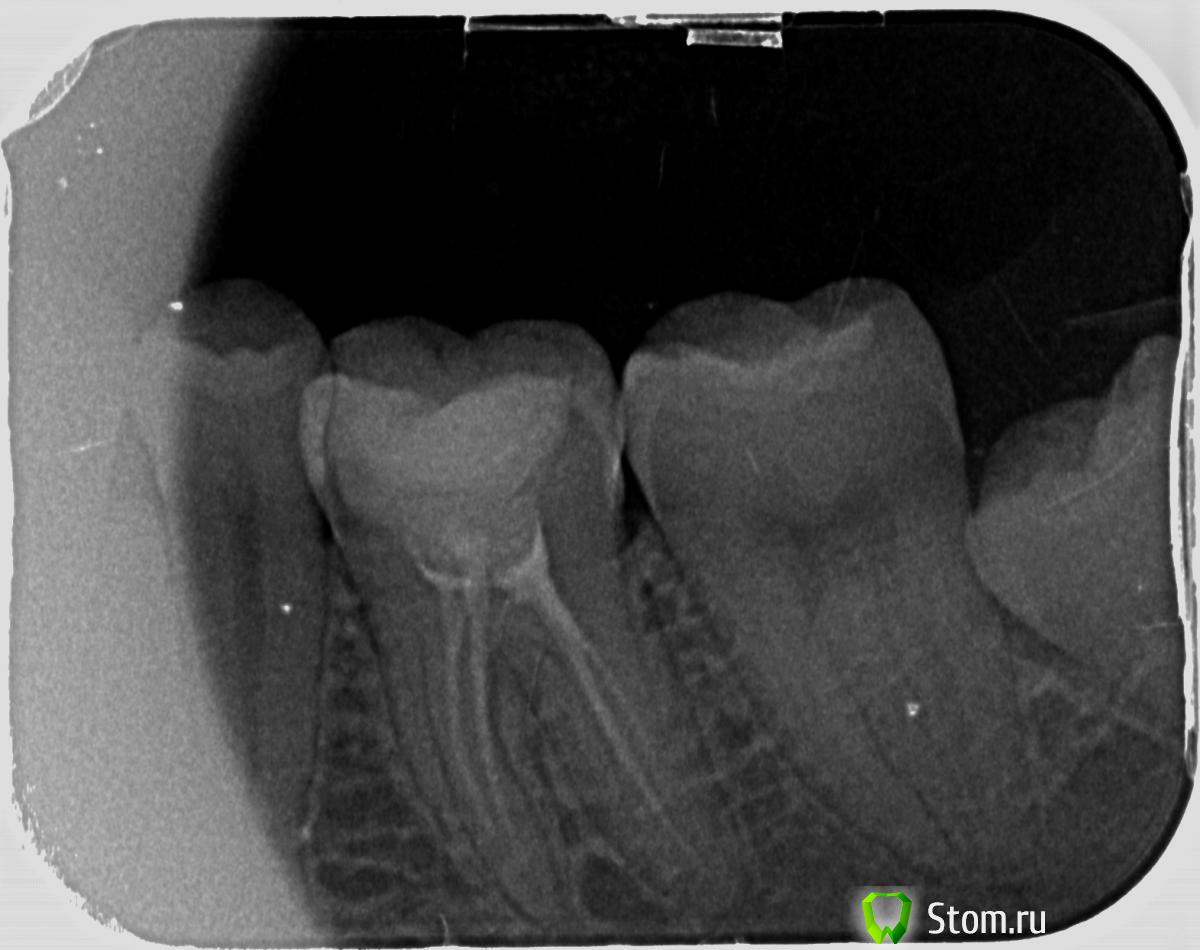

Юляшик Опубликовано 16 декабря, 2011 Поделиться Опубликовано 16 декабря, 2011 В июне этого года мне удалили нерв в 36 зубе (пульпит был). Однако зуб реагирует на холодное, горячее, порой просто на прикосновение. Временами боль усиливается, а временами - исчезает. Стоматолог, который лечил пульпит, сказал, что у меня с ним всё хорошо. В частной стоматологии мне сказали, что каналы запломбированы плохо, и из-за этого зуб болит. Это последний снимок, который мне сделали в частной клинике. Ссылка на комментарий

ger_berra Опубликовано 16 декабря, 2011 Поделиться Опубликовано 16 декабря, 2011 Правильно сказали,что каналы плохо запломбированы.Перелечивать надо. Ссылка на комментарий